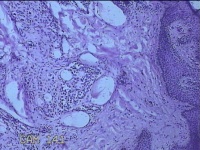

右侧头部息肉结节

性别

男

年龄

39岁

临床诊断

头皮良性肿瘤

一般病史

发现右侧头部息肉结节20余年。

标本名称

右侧头部息肉组织

大体所见

灰白暗红色组织1.2x1x0.8cm一块,表面带梭形皮肤1.2x0.8cm,皮下见结节1.2x0.9x0.3cm一个,切开结节呈实性,切面灰白暗红色,质软。